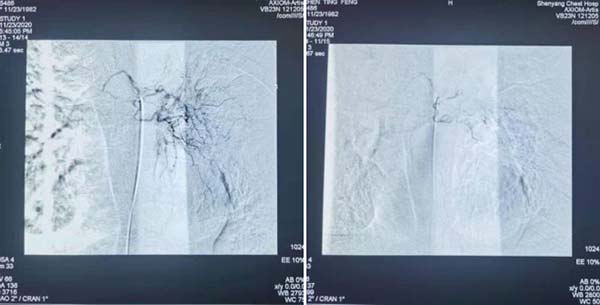

应用C2导管超选左侧支气管动脉后栓塞。

应用C2导管超选左侧胸廓内动脉后栓塞。

最后应用猪尾管于左右肺动脉主干造影,未见出血血管。